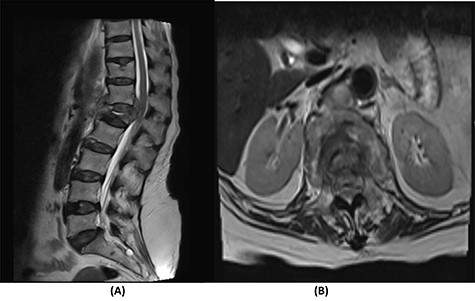

Radiological and laboratory investigations for possible malignancy or infection were done, and results were negative for malignancy. Erythrocyte sedimentation rate (ESR) was 50 mm/h and C-reactive protein (CRP) level was 38 mg/l. A magnetic resonance imaging (MRI) scan of the spine with contrast showed a significant pathological fracture of L1 along with spinal cord compression (Fig. 1). The patient underwent posterior spinal decompression of T12–L1 and pedicle instrumentation of T11–L3 with tissue and bone biopsy.

(A) T2-weighted sagittal lumbar spine MRI demonstrating a pathological fracture of L1 with spinal canal and neural foramina stenosis and cord edema and epidural and prevertebral soft tissue components. (B) T2-weighted axial lumbar spine MRI of the corresponding level of L1 vertebral body.